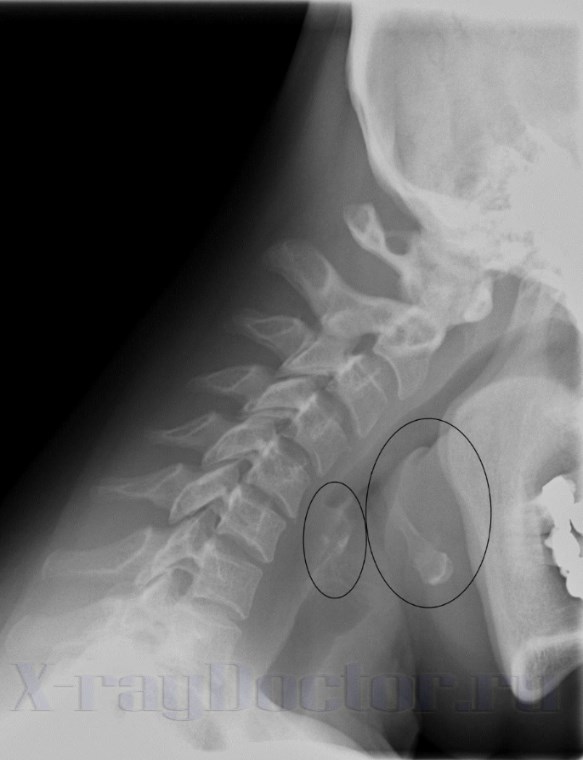

Рентген аденоидов на глубине в 20 мм показывает фронтальный разрез гортани. На нем четко прослеживаются:

- просветы валлекул;

- черпалонадгортанные складки;

- надгортанник;

- голосовые связки;

- гортанные желудочки;

- пластинки щитовидного хряща;

- дужка перстневидного хряща.

На томограмме со срезом на 20 мм четко прослеживаются грушевидные синусы. Они смещаются или деформируются при ларингите, коклюше, дифтерии, опухоли и туберкулезе.